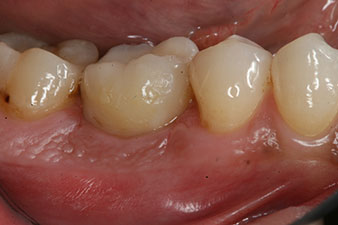

Die Abschlussbilder zeigen die verschraubte monolithische Kompositkrone in situ und die Röntgenkontrolle (Abb. 9 und 10) (6).